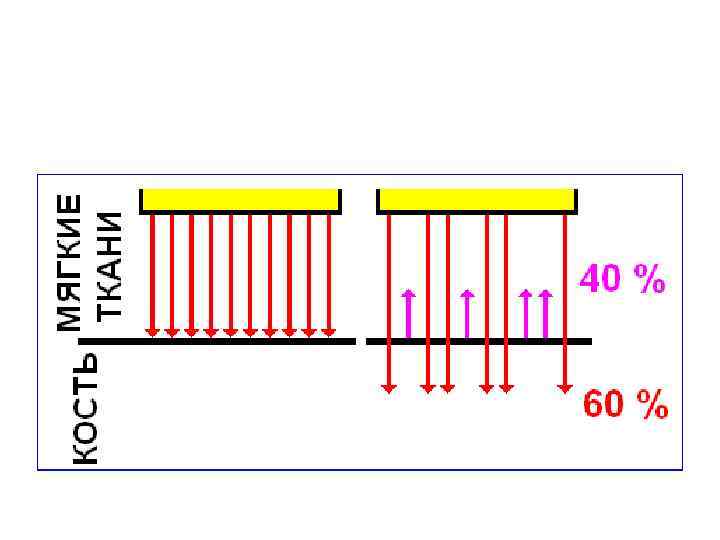

Коэффициент отражения • зависит от разности импеданса соприкасающихся сред, т. е. от степени акустической неоднородности граничащих тканей. • чем выше различие в импедансе, тем больше волн отражается.

Коэффициент отражения • зависит от разности импеданса соприкасающихся сред, т. е. от степени акустической неоднородности граничащих тканей. • чем выше различие в импедансе, тем больше волн отражается.

«Слепые» зоны • наполненные воздухом легкие, • кишечник (при наличии в нем газа), • участки тканей, расположенные за костями.

«Слепые» зоны • наполненные воздухом легкие, • кишечник (при наличии в нем газа), • участки тканей, расположенные за костями.